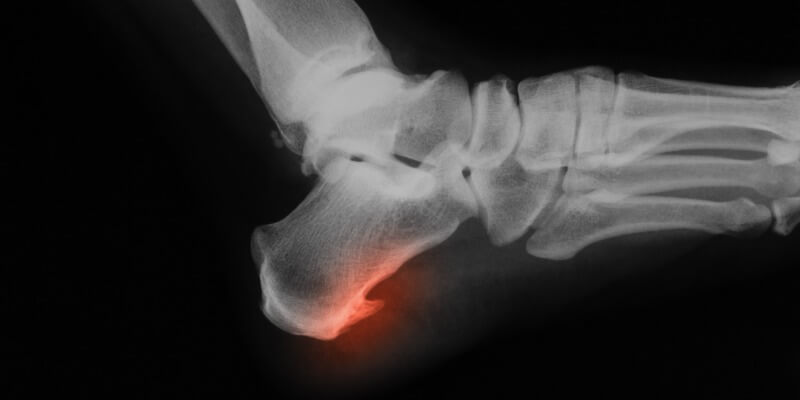

A bone spur is a bony outgrowth that can occur on any bone in the body. They are most commonly found on the spine, shoulders, hands, and feet. Bone spurs can be caused by arthritis, wear, and tear, or injury.

There are several tests that can be used to diagnose bone spurs. An X-ray is often the first test ordered because it can show whether there are any bony outgrowths. A CT scan or MRI may also be ordered to get a more detailed view of the bone spur. A biopsy may also be done to rule out other conditions.